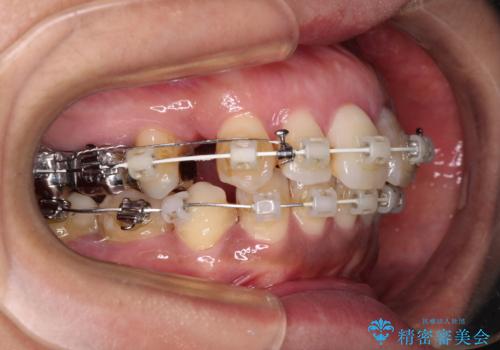

- 矯正装置

- 審美装置

- 治療期間

- 2年3ヶ月

- 治療回数

- 10-30回